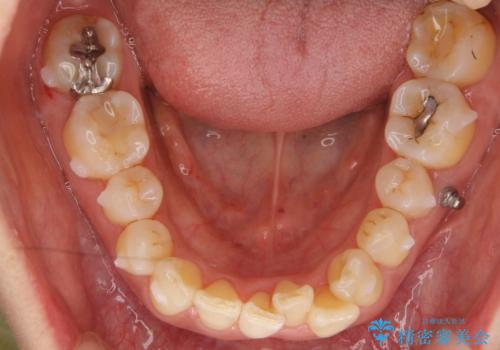

左下の前歯を中に入れるスペースを確保する目的で左下の奥歯を後ろ移動させました。

また、左下の小臼歯の捻転はマウスピースで治りにくいため、

事前にワイヤーによる部分矯正を行い、矯正用ミニスクリューを植立しています。